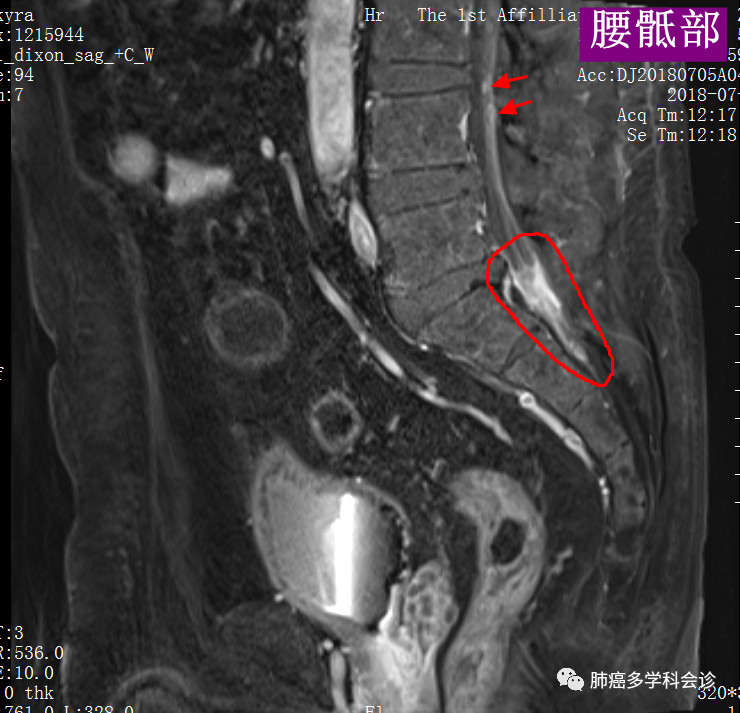

我们再把上图的局部进行放大,以更好显示转移灶:

腰髓、骶髓:5.jpg